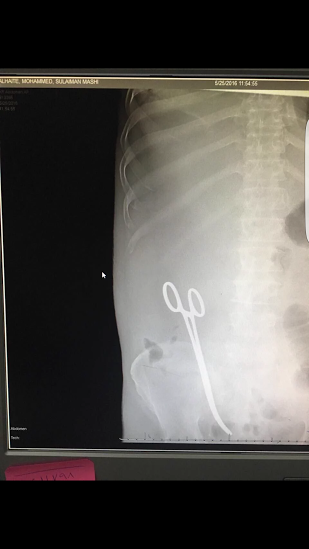

أعلنت صحة حائل منع المتورطين في حادث نسيان مقص في بطن مريض من السفر، وتسجيل الحادث ضمن برنامج الأحداث الطبية الجسيمة في وزارة الصحة.

ونشرت صحة حائل بيانًا- قبل قليل- على لسان مدير إدارة العلاقات العامة والإعلام والمتحدث الرسمي بصحة حائل عارف بن غازي الشمري، جاء فيه: إشارة إلى ما تم تداوله عبر المواقع الإعلامية ووسائل التواصل الاجتماعي والاستفسارات المرسلة حول نسيان مقص داخل بطن مريض أثناء عملية جراحية له، تود المديرية العامة للشؤون الصحية بمنطقة حائل بداية أن تأسف وتقدم اعتذارها لما حدث للمريض.

وقالت المديرية: إنه فور العلم بذلك تم الإبلاغ عن هذا الحدث الجسيم فور وقوعه وتسجيله عبر برنامج الأحداث الطبية الجسيمة في وزارة الصحة، وكذلك تم توجيه مدير عام الشؤون الصحية بالمنطقة بالتحقيق في أسباب حدوث ذلك وملابساته ومحاسبة المتسبب فيه.

وأضافت: نود أن نوضح أنه قد تم منع جميع من شارك بهذا الخطأ من الممارسين الصحيين المتعاقدين من السفر حتى انتهاء التحقيق.